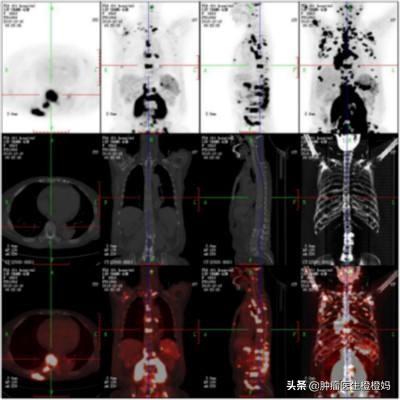

- PET/CT:骨髄の微小転移を示すことができるので、より良好な患者さんにはこの検査をお勧めします。つまり、骨転移が非常に小さいときに発見できるのです。さらに、体の他の部分に転移があるかどうかも同時に判断できる。患者の状態をより包括的に評価する。。

2.画像検査では、X線検査は早期の骨破壊を検出することができ、腫瘍は骨皮質を突き破った後、軟部組織塊を生成することができます、必要に応じてX線検査に加えて、CT、磁気共鳴レベル検査またはPET-CT検査を実施する必要があります;

実際、今はスクリーニングの技術もかなり向上していますし、例えばペットCTという全身性のスキャンをすることで、骨であろうが血液であろうが、他の部位であろうが、基本的にはペットCTをすることで、全身との関係で全身の状態を把握することができ、そのような病変を早期に発見できる場合も多々あります。